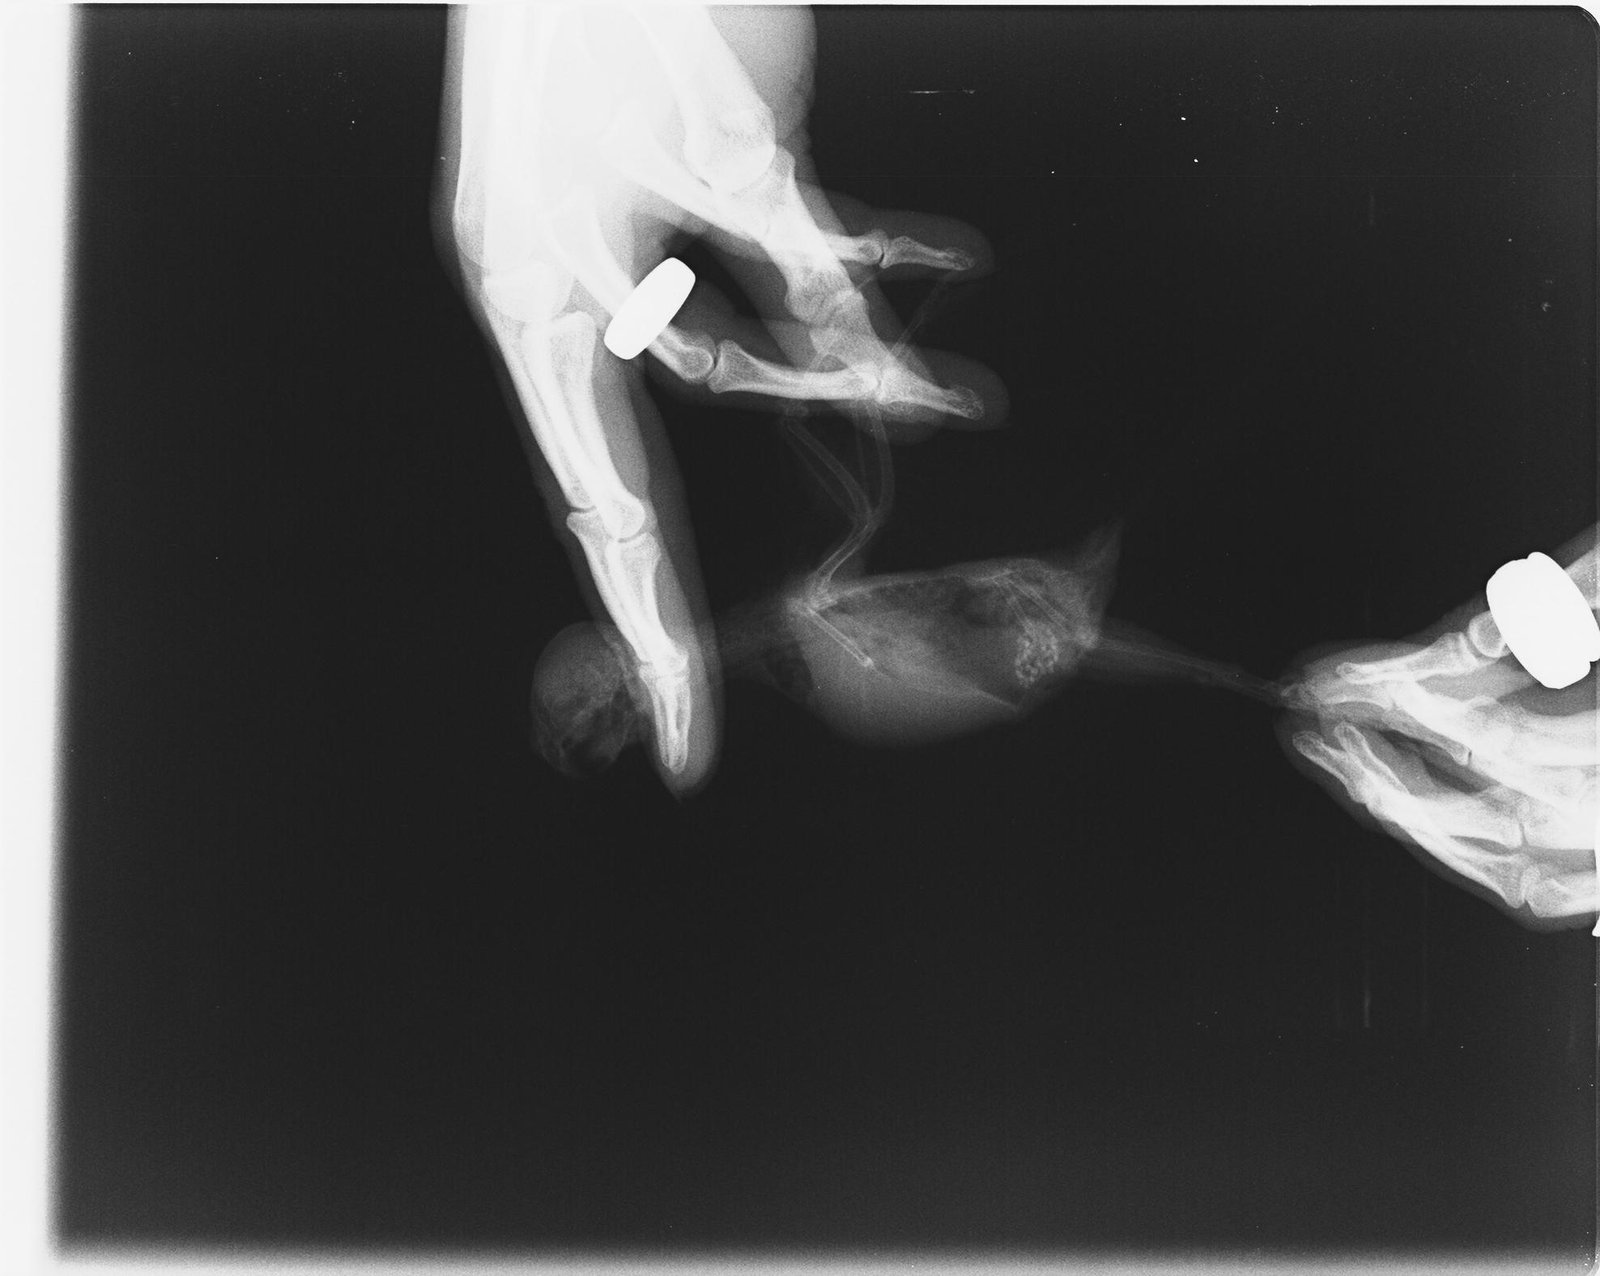

Добрый день! Побывали вчера у орнитолога Лешковой М.А, замечательный доктор. К сожалению, рентген показал онкологию семенников, достаточно крупную. Все будет зависеть от того, насколько быстро она будет расти, врач сказала что живут птички с таким и по 6 лет. Через 4 месяца поедем на повторный рентген - будем мониторить динамику роста опухоли. Анализ подтвердил мегабактериоз. Назначенное лечение: Нистатин 500.000 1/2 таб. на 1 мл. воды по 0,1 мл. 2 раза в день - 45 дней. Дифлюкан порошок, развести по инструкции, давать по 0,06 мл. 2 раза в день - 30 дней. Локсиком суспензия 0,5 мг/мл. - по 0,09 мл. 2 раза в день, поить постоянно на протяжении жизни. Докармливать кашей Hainz безмолочной - 38 градусов. Строгая диета, исключить обычный корм и мин. песок, кормить запаренным овсом. В июле на повторный анализ и осмотр.

Фото рентгена и анализа прилагаю, как обещала: